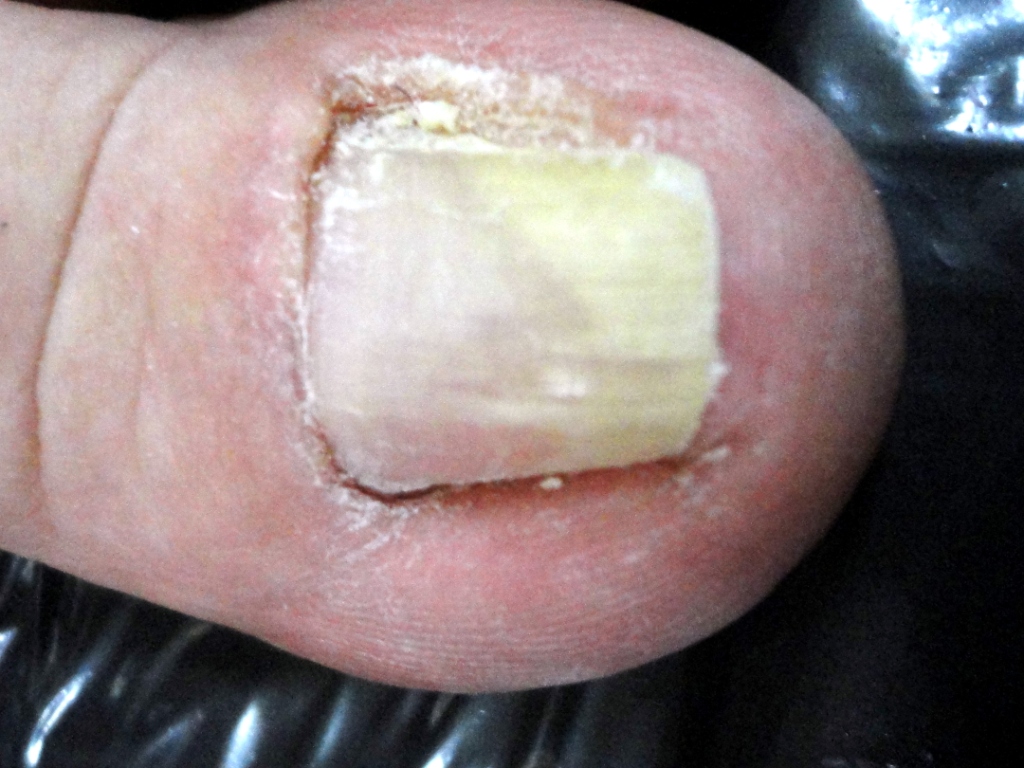

Relatamos um caso de mulher, 51 anos, com história de longa duração de alterações no aspecto da unha do hálux esquerdo e dor local intensa. Após diversos tratamentos, já com o diagnóstico de verruga subungueal, foi suspeitada a existência de tumor glômico pela história clínica e testes semiológicos sugestivos. Foi realizada cirurgia, com a confirmação histopatológica das duas hipóteses.

O tratamento é cirúrgico, tratando a dor e evitando a recorrência. O presente caso relata associação de diagnósticos (tumor glômico e verruga subungueal) culminando com as importantes alterações no aspecto da unha.